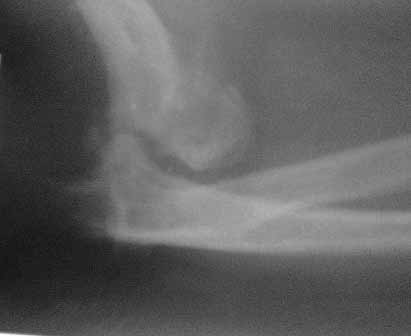

Пациент 45 л. Обратился к нашему доктору с жалобами на боли и ограничение движений в правом локтевом суставе, под углом 140гр., движения качательные, болезненные.

Травму получил 7 месяцев назад. Д-з " застарелый задненаружный вывих предплечья"

В предварительном плане артродез в функционально выгодном положении, или резекция сустава - хоть какие-то будут движения. Может быть, метод Илизарова ?